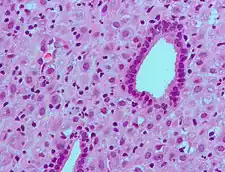

The endometrium consists of a single layer of columnar epithelium plus the stroma on which it rests. The stroma is a layer of connective tissue that varies in thickness according to hormonal influences. In the uterus, simple tubular glands reach from the endometrial surface through to the base of the stroma, which also carries a rich blood supply provided by the spiral arteries. In women of reproductive age, two layers of endometrium can be distinguished. These two layers occur only in the endometrium lining the cavity of the uterus, and not in the lining of the fallopian tubes.[4][5]

- The functional layer is adjacent to the uterine cavity. This layer is built up after the end of menstruation during the first part of the previous menstrual cycle. Proliferation is induced by estrogen (follicular phase of menstrual cycle), and later changes in this layer are engendered by progesterone from the corpus luteum (luteal phase). It is adapted to provide an optimum environment for the implantation and growth of the embryo. This layer is completely shed during menstruation.

- The basal layer, adjacent to the myometrium and below the functional layer, is not shed at any time during the menstrual cycle. It contains stem cells that regenerate the functional layer,[1] which develops on top of it.

It is possible to identify the phase of the menstrual cycle by reference to either the ovarian cycle or the uterine cycle by observing microscopic differences at each phase—for example in the ovarian cycle:

| Phase | Days | Thickness | Epithelium |

|---|---|---|---|

| Menstrual phase | 1–5 | Thin | Absent |

| Follicular phase | 5–14 | Intermediate | Columnar |

| Luteal phase | 15–27 | Thick | Columnar. Also visible are arcuate vessels of uterus |

| Ischemic phase | 27–28 | Columnar. Also visible are arcuate vessels of uterus |